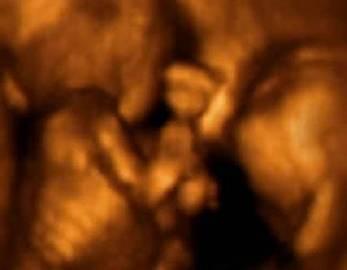

第二张图片中双胞胎已经发育出了婴儿的大致雏形,可以清晰的看到宝宝的头部和胳膊的轮廓。接下来则是宝宝发育的下一个阶段,已经可以看到宝宝发育的手指细节。